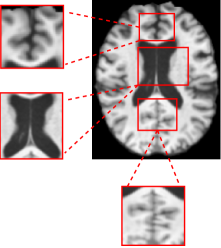

Here, the negation of the output followed by a minimum operation is mathematically equivalent to erosion [23]. Finally, the foreground mask MM is reapplied to restrict updates to valid tissue regions only. This method enables the network to learn how to apply erosion-like transformations in a differentiable way. The resulting output is expected to resemble more advanced cases of AD (Fig. 4).

Refer to caption

(a)

(b)

Figure 4: Visualization of a pseudo-erosion result. (a) Original AD image from the dataset. (b) Resulting image after applying the pseudo-erosion module, showing features akin to more severe AD.